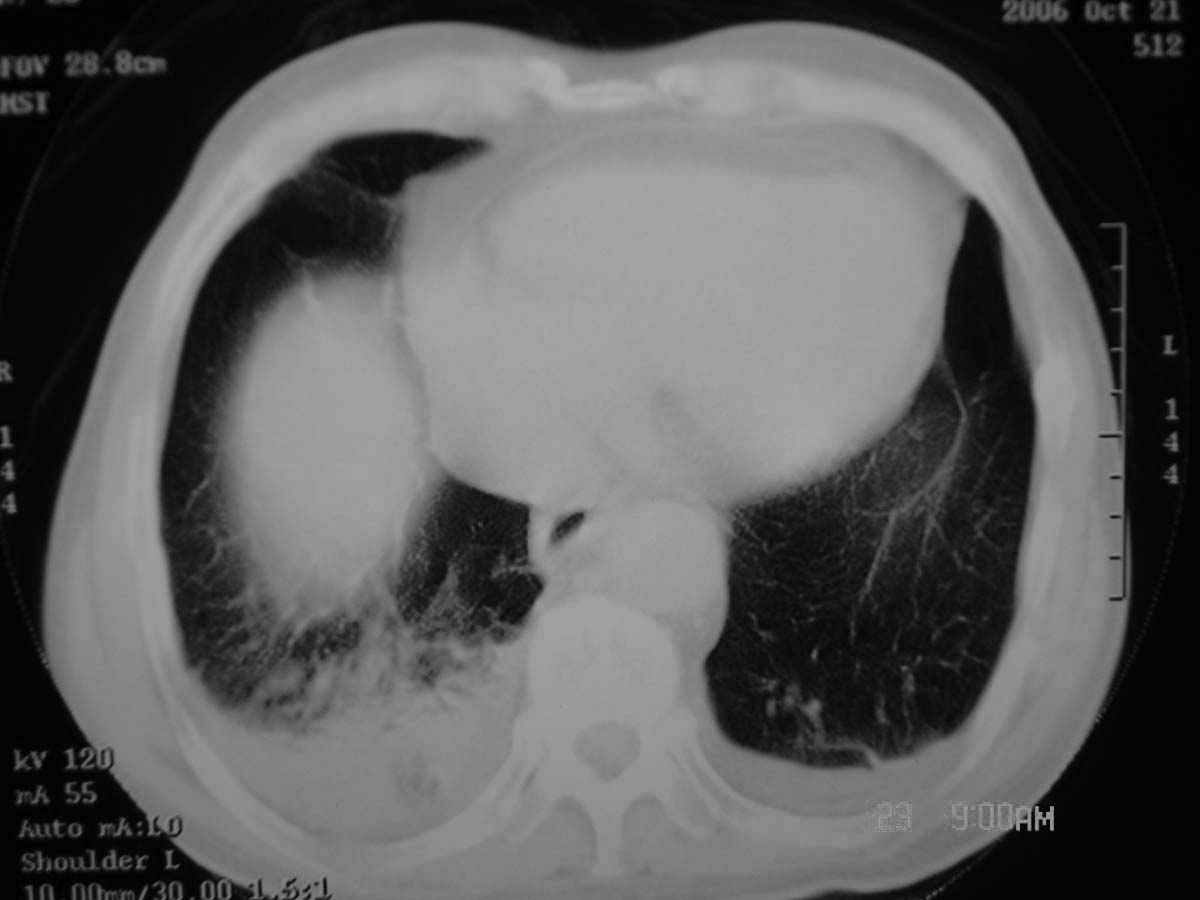

以下是引用守望可可西里在2006-11-23 14:33:00的发言:[br][br] 糖尿病病人很容易继发结核,病人又有双侧胸膜增厚、粘连、胸腔积液以及双上肺的斑片状、条索状影结核病灶影,以一元论考虑,右下肺病变首先考虑干酪性肺炎,可以正规抗炎治疗后复查,排除一般的肺炎。